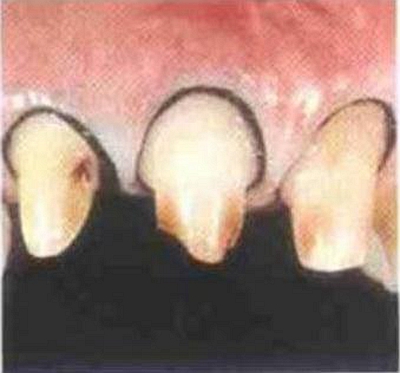

內(nèi)冠邊緣懸突是導(dǎo)致牙齦變色的"罪魁禍?zhǔn)?quot;

肩臺懸突易出現(xiàn)繼發(fā)齲

冠邊緣的位置要放在一個適合的位置,齦溝的深度在患者口中會有很大不用,深度因人而異,尤其是存在牙齦或牙周炎癥的患者。其齦溝會有超過2mm的深度,絕大部分會小于1mm,冠邊緣不要損傷上皮性附著,這樣就會引起齦炎。

肩臺的外形應(yīng)與釉牙骨界相適應(yīng):注意備牙時上皮性附著在牙的不同側(cè)面的弧線各不相同。不要把肩臺備成平的,要與釉牙骨質(zhì)界的弧線相適應(yīng),只有嚴(yán)格遵守這一點才可以避免破壞上皮性附著而導(dǎo)致牙齦炎癥,進(jìn)而牙齦萎縮。